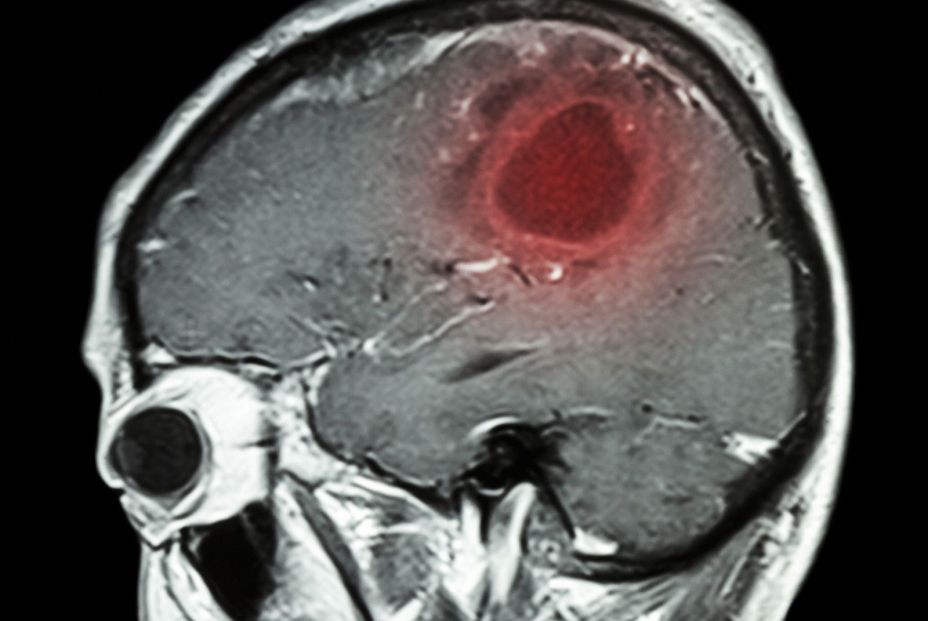

No causan tumores cerebrales

Al mismo tiempo de publicarse este ensayo ha salido otro en el que los móviles salen mejor parados. Como recoge Reuters, la OMS confirma que no hay relación entre los smartphones y los tumores cerebrales

Un nuevo informe, cuya redacción ha sido coordinada por la Agencia Australiana de Protección contra las Radiaciones y Seguridad Nuclear (ARPANSA, por sus siglas en inglés) afirma que, aunque el uso de la tecnología inalámbrica ha aumentado enormemente en los últimos 20 años, no se ha producido un incremento de la incidencia de tumores malignos en la cabeza.

"Las ondas analizadas son las radiaciones electromagnéticas comprendidas entre 300 Hz y 300 GHz; mismas que se utilizan para la comunicación por smartphones, pero también en televisores, radios, monitores de vigilancia para bebés, conexiones Wi-Fi, y que se emplean para aplicaciones industriales y médicas", explica Mark Elwood, coautor del estudio y profesor de epidemiología del cáncer en la Universidad de Auckland, en Nueva Zelanda. En el tiempo de estudio, los expertos no constataron ningún aumento en la incidencia de tumores cerebrales, ni de otras neoplasias craneales como los de la hipófisis o de las glándulas salivales; lo mismo ocurrió con la leucemia.